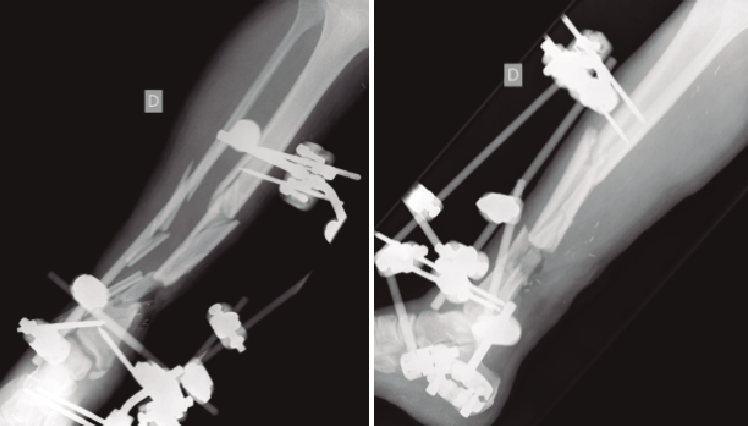

Figura 1. Paciente con fractura del tercio distal de la tibia de tipo Gustilo IIIC que se trató inicialmente con fijador externo.

Figura 2. Pasados 6 meses, se observa ausencia de consolidación de la fractura. El paciente presentaba además supuración de pines distales y clínica infecciosa.

Figura 3. Rescate de la fractura mediante fijador externo de tipo Ilizarov, empleado como tratamiento puente antes del tratamiento definitivo.

Una vez establecido el diagnóstico, el tratamiento será, si las condiciones del paciente lo permiten, fundamentalmente quirúrgico (Figuras 1 a 4).

Figura 4. Una vez confirmada la erradicación de la infección, se procedió a la retirada del fijador externo. Se realizó un aporte de injerto óseo autólogo procedente de la tabla interna de la tibia y una posterior fijación interna de la fractura mediante una artrodesis de tobillo. El resultado final fue una correcta consolidación de la fractura.